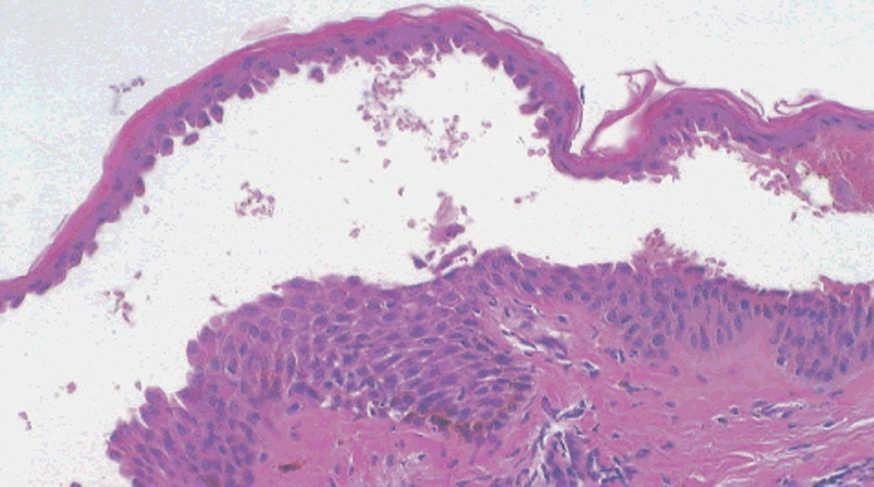

La primera alteración que se observa en la histopatología del PV es un edema intercelular que se localiza en las capas más inferiores de la epidermis, con desaparición de los puentes intercelulares, conduciendo así al fenómeno de acantolisis. Cuando la acantolisis progresa da lugar a la ampolla intraepidérmica suprabasal cuyo suelo está formado por una hilera de células basales, que se ha dicho que se disponen como una «hilera de lápidas sepulcrales», y cuyo techo se encuentra constituido por el resto de la capa espinosa, las capas granulosas y la córnea (fig. 19). En el interior de la ampolla se suelen encontrar queratinocitos acantolíticos, bien de manera aislada o en grupos, con una apariencia característica, cuya morfología es redondeada en lugar de poligonal, con un núcleo pequeño e hipercromático, con frecuencia rodeado de un halo y citoplasma homogéneo.

Fig. 19.--Ampolla suprabasal de pénfigo vulgar.